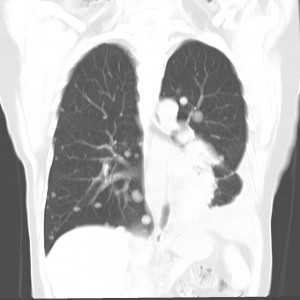

Выявляемые изменения зависят от подтипа опухоли, но должны включать что-либо из ниже изложенных типичных признаков хондросаркомы. В основном, хондросаркомы, к моменту диагностики имеют крупные размеры, обычно более >4 см в диаметре (более 10 см в 50% случаев).

Рентгенография

- деструкция (50%)

- интраоссальная кальцинация: ~70% (по типу колец и арок или по типу попкорна) : поражение более чем на две трети толщины кортикального слоя (с сравнением с энхондромой, при которой фестончатость распространяется менее чем на две трети)

- рисунок изъеденный молью при высокой степени

- ремоделирование и истончение надкостницы, периостальная реакция являются полезными признаками в дифференциальной диагностике между энхондромой и хондросаркомой низкой степени злокачественности

Обобщено, при компьютерной томографии мы видим те же признаки, что и при рентгенографии, но с лучшей их визуализацией: